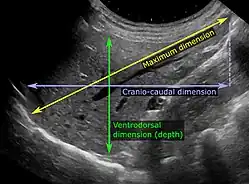

Chez les patients dont les tests de la fonction hépatique sont perturbés, l'échographie peut montrer une augmentation de la taille du foie (hépatomégalie), une réflectivité accrue (qui pourrait, par exemple, indiquer une cholestase), des maladies de la vésicule biliaire ou des voies biliaires ou une tumeur du foie. L'échographie des tumeurs hépatiques comporte deux étapes : la détection et la caractérisation[réf. nécessaire]. La détection des tumeurs est basée sur les performances de la méthode et doit inclure des informations morphométriques (dimensions sur trois axes, volume) et des informations topographiques (nombre, emplacement spécifiant le segment hépatique et le lobe/lobes). La spécification de ces données est importante pour la stadification des tumeurs hépatiques et le pronostic[réf. nécessaire]. La caractérisation de tumeur est un processus complexe basé sur une somme de critères menant vers la définition de nature de tumeur. Souvent, d'autres procédures de diagnostic, notamment interventionnelles, ne sont plus nécessaires. La caractérisation tumorale par la méthode échographique sera basée sur les éléments suivants : consistance (solide, liquide, mixte), échogénicité, aspect structurel (homogène ou hétérogène), délimitation du parenchyme hépatique adjacent (capsulaire, imprécis), élasticité, effet de rehaussement acoustique postérieur, la relation avec les organes ou structures de voisinage (déplacement, invasion), la vascularisation (présence et caractéristiques en échographie Doppler et en échographie de contraste (ECUS)[réf. nécessaire].